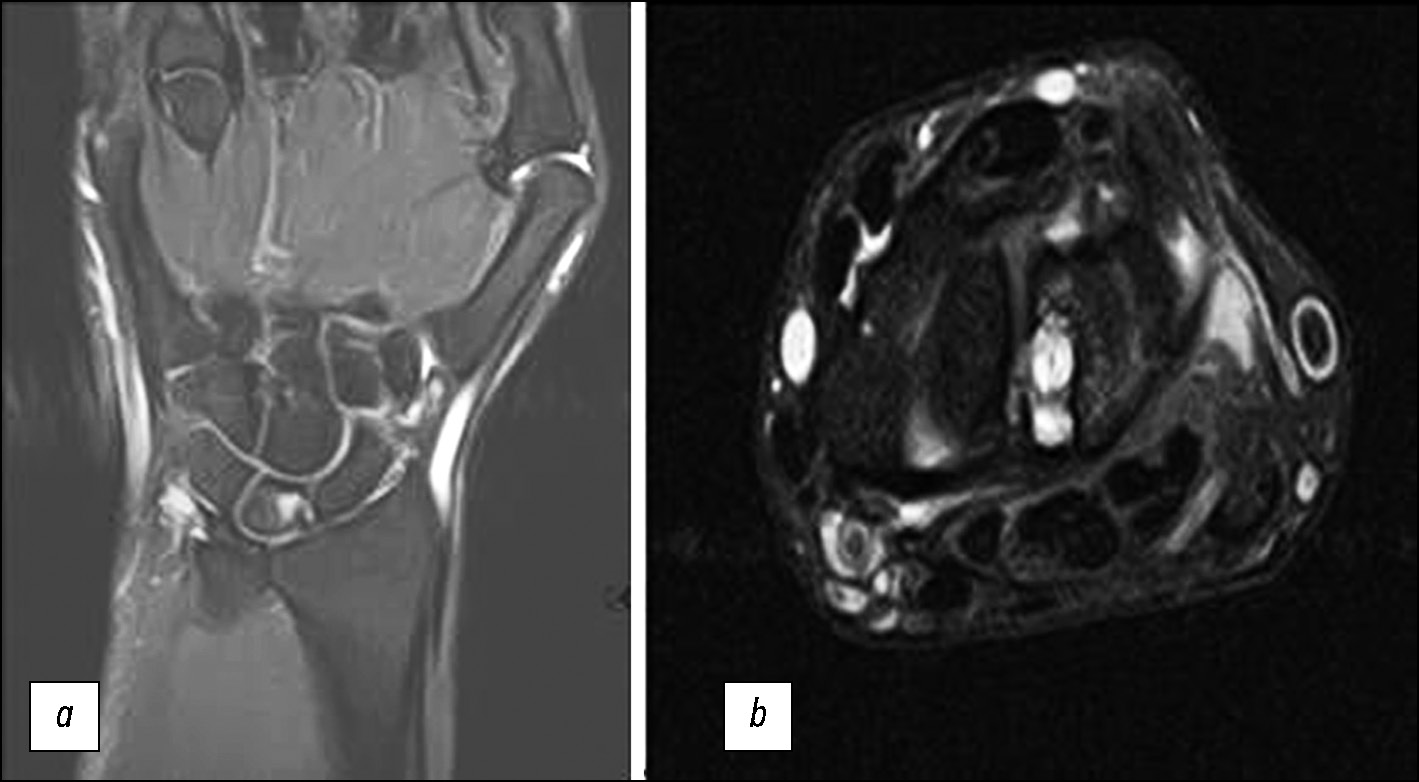

Images with Artifacts

A review of hand MRI showed that MRI scans may often be of low diagnostic value, with low resolution and low contrast enhancement (low SNR), and present motion or metal artifacts in the scan field (Fig. 8–10).

Fig. 8. Reduced imaging quality because of movement artifacts without using a splint (arrows); (a) T1-weighted images in the coronal plane; (b) STIR protocol in the coronal plane.

Fig. 9. Reduced imaging quality in a patient with triangular fibrocartilage complex disorder because of motion artifacts (arrows) and atypical positioning (without a splint); (a) T2-weighted images in the coronal plane; (b) PD-weighted images with fat suppression in the sagittal plane.

Fig. 10. Reduced imaging quality because of technical artifacts from the ring: T1-weighted images in the coronal plane.